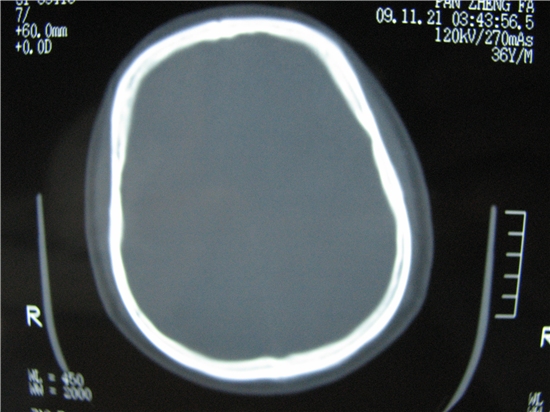

标题: CT23231:男 32岁 车祸伤,鼻腔内出血明显。 [打印本页]

标题: CT23231:男 32岁 车祸伤,鼻腔内出血明显。

额窦内及额部软组织内可见多发游离类骨质密度影,考虑额骨骨折可能。

额窦内应该是正常的,和体位有关系,当你用三位重建就知道了

额窦致密骨瘤,前额部及右顶部头皮损伤伴异物存留

左侧额骨、鼻骨骨折,额窦内的应该是游离骨块